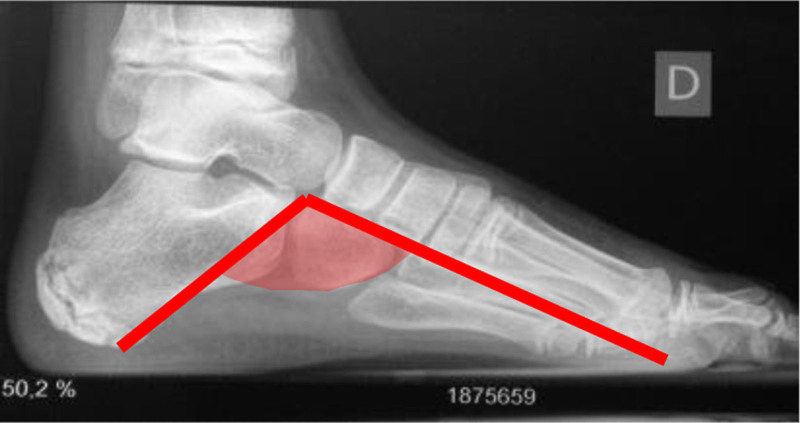

The objective of this study is to describe and evaluate dorsal hemiepiphysodesis of the first metatarsal as an osteotomy replacement technique. Retrospective analysis of patients with pes cavovarus (PCV) treated in our center with dorsal hemiepiphysodesis of the first metatarsal. Meary's angle, calcaneal pitch, and Moreau Costa Bartani were compared pre and post-operatively and the ratio between width and foot length was monitored. Between May 2012 and May 2022, eight patients (14 feet) with PCV underwent dorsal hemiepiphysiodesis of the first metatarsal combined with the Steindler procedure. Four patients (50%) were male. The average age for boys at surgery was 10.75 years (10-11) and for girls was 9.75 years (8-11). Most patients (87.5%) had idiopathic PCV and 12.5% had a neurological PCV. Median follow-up was 4.3 years (1.5-10) and a benefit was seen in all patients in Moreau Costa Bartani angle (112.64° vs. 120.59°; P value = 0.003), calcaneal pitch (26.48° vs. 25.36°; P value = 0.091) and Meary's angle (10.60° vs. 5.36°; P value = 0.008) after surgery. Supination improvement was also shown (0.21 vs. 0.24; P value = 0.039). Despite the limited number of patients, the results demonstrated that dorsal hemiepiphysiodesis of the first metatarsal can be a valid alternative to osteotomy of the base of the first metatarsal, with less morbidity and a gradual and dynamic correction throughout growth.

Abstract Image